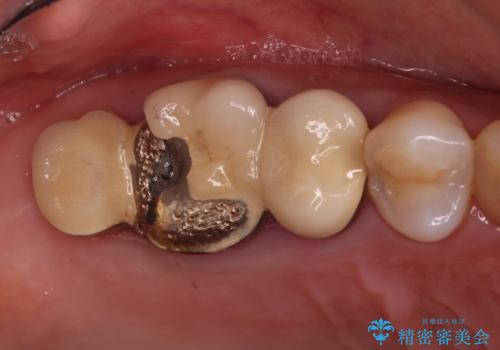

- 歯が欠損したままの奥歯のクラウンが欠けているとのことで来院された患者様です。

右上の一番奥の歯が欠損しており、その手前の歯2つを土台に連結されたクラウンが装着されていました。

不安定な咬み合わせとなっており、クラウンの表面が剥離していたため、インプラントによる欠損補綴治療を行い、手前2つの歯も一緒に補綴治療を行うこととしました。